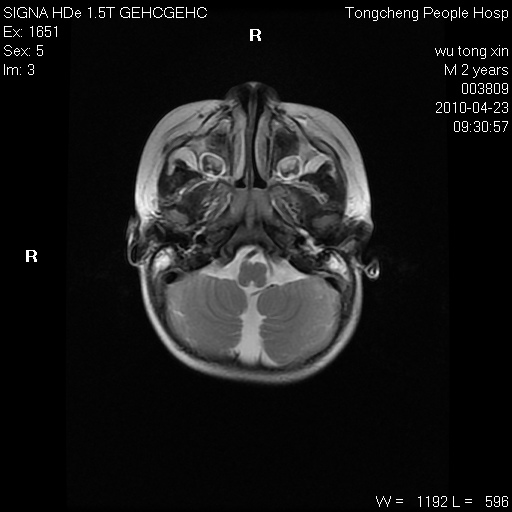

以下是引用赵物学在2010-4-25 12:43:00的发言:[br]巨脑回[br]侧脑室后角低密度影考虑hie或肾上腺脑白质营养不良?[br][br][本贴已被 赵物学 于 2010-4-25 12:51:28 修改过]

以下是引用gaoxiao在2010-4-25 16:54:00的发言:[br]巨脑回畸形。脑白质髓鞘化不良

以下是引用pujunzhi在2010-4-25 21:35:00的发言:[br]考虑 1双侧大脑皮质发育不良 2轻度脑积水 3双侧脑室后角旁片状长t1长t2信号,需继续观察,因为正常小儿此处脑白质的髓鞘化时间可以延迟到4-6岁,才显示正常。